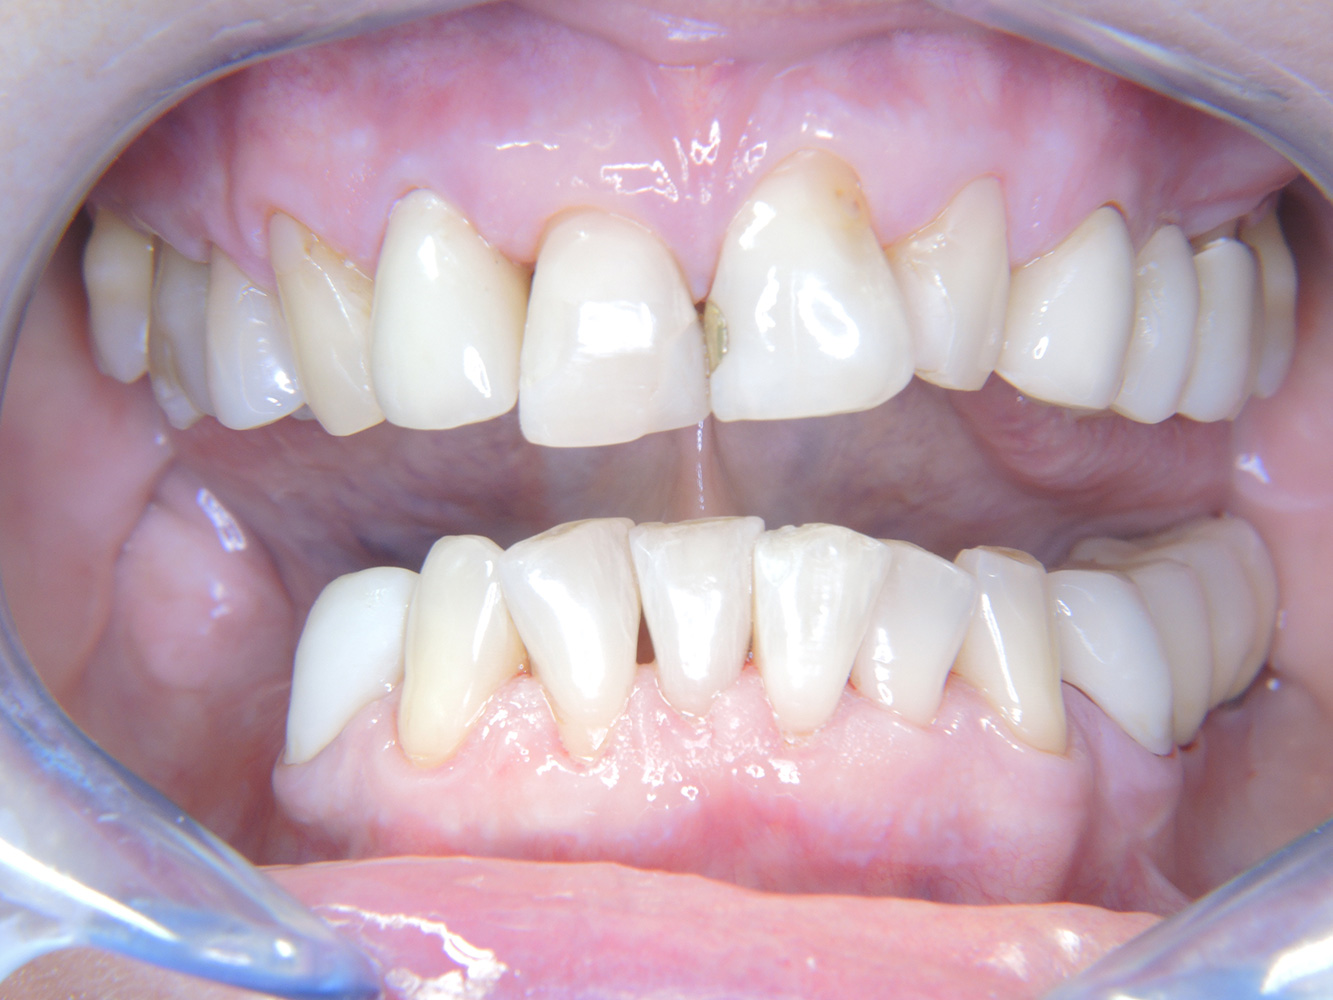

The 68-year-old patient has no general health conditions and is not taking any medication that may be relevant to her oral health, and her lifestyle does not pose any particular risk. The patient has two dental implants (3rd quadrant, for five years) and a previous case of periodontal disease (stage IV, grade B periodontitis) with tooth loss. Currently the periodontal conditions are stable. However, periodontitis significantly increases the biological complications of implantations and there is a risk of implant loss (21). Four recommendations can be determined for the prophylaxis session.

As the patient does not have any particular risk factors with specific dental implications, the requirements determined from her current state of oral health are crucial. Here, it is recommended that a thorough assessment of periodontal condition be carried out once a year. This will ensure that any potential progression of the previous periodontal disease or development of peri-implantitis can be responded to in good time.

Despite the stable conditions, it is also crucial for the instructive/motivational discussion to be conducted with this patient. Particular attention should be paid to teaching the patient how to care for the implants correctly. Here in particular, good at-home maintenance can have a significant impact on the long-term stability of oral and implant health.

Because the patient has implants and a history of periodontal disease, she is at risk of developing peri-implantitis. It is therefore recommended that she attend a recall session every three to four months.